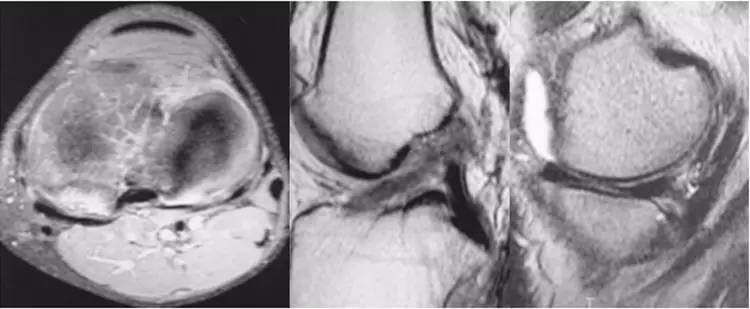

ACL损伤的MRI分级——

Grade1:韧带内损伤,无长度改变。

Grade2:韧带内损伤并长度延长。

Grade3:完全性韧带撕裂。

Grade1、2级为韧带的部分损伤,Grade3级为韧带的完全断裂。

4.gif

ACL最好的观察层面:最好的观察层面是斜矢状面,同时需要结合横断面和冠状面。

5.gif